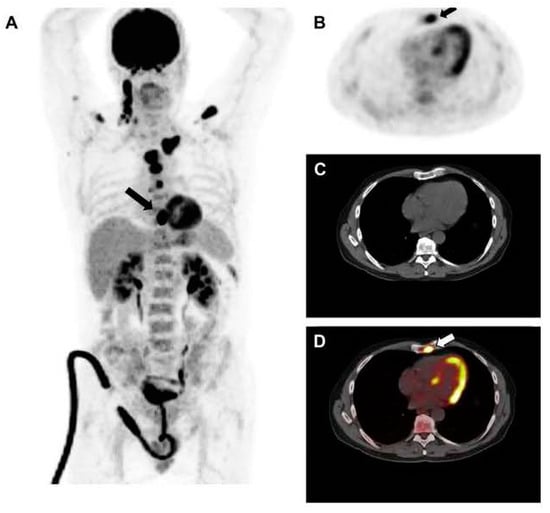

Evaluating the response to treatment is a significant area where [18F]FDG PET/CT might offer greater utility compared to conventional imaging methods [23] (Figure 4 and Figure 5). By analyzing the metabolic behavior in areas with clonal plasma cell growth, [18F]FDG PET/CT can precisely gauge and quantitatively measure alterations in cancer cell activity following therapeutic interventions [24,25,26,27,28,29]. Furthermore, there is a robust correlation between negative [18F]FDG PET/CT results and a highly positive response to treatment in myeloma patients [20].

Figure 4.

This figure presents the case of a 39-year-old patient with symptomatic multiple myeloma (MM) who was being prepared for high-dose therapy (HDT) and autologous stem cell transplantation (ASCT). This patient underwent an [18F]FDG PET/CT scan both before and after treatment. The maximum intensity projection (MIP) of the [18F]FDG PET/CT scan before treatment (A) revealed a combination of intense, widespread uptake in the axial skeleton and multiple focal bone marrow lesions in locations such as the sternum, ribs, humerus, scapula, and femur (indicated by arrows). The follow-up [18F]FDG PET/CT MIP after HDT and ASCT (B) demonstrated a complete remission of both the diffuse bone marrow uptake and the focal MM lesions. Figure 2, PMID: 31905752, PMCID: PMC6982887, OPEN ACCESS.

Figure 5.

This figure is displaying the baseline (A,B) and follow-up (C,D) [18F]FDG PET images of a patient with MM before high-dose chemotherapy and 2 months post-treatment. The [18F]FDG uptake by the lesions was quantified using an adaptive thresholding algorithm. The image was sourced from PMID: 31084773 (Figure 3), and permission was granted for its use.